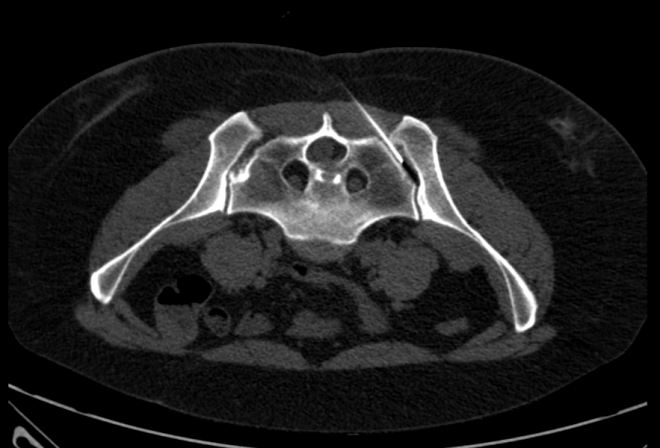

Po punkci levého SI skloubení pod CT kontrolou (obr.1) s podáním malého množství kontrastní látky bylo podáno RF (74 MBq Rhenium 186 sulhide susp.), poté aplikován depotní kortikoid a anestetikum.

/ Obr.1.: Aplikace RF pod CT kontrolou – levé SI skloubení. /